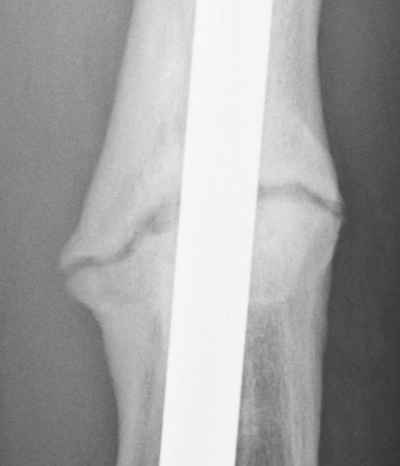

Jan. 31, 2006 Aug. 17, 2006 Apr. 17, 2007 Feb. 21, 2008